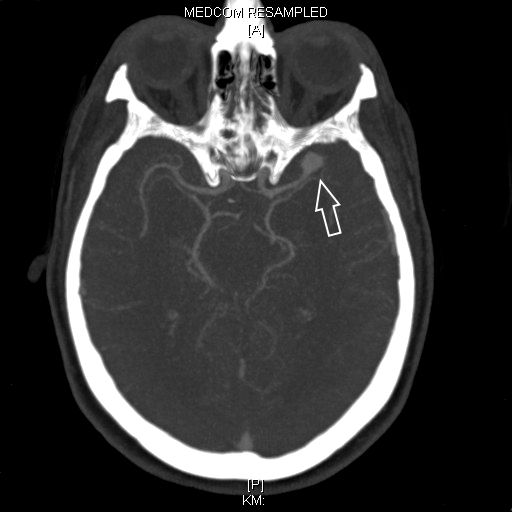

Als schnellste und sicherste Maßnahme gilt das craniale Computertomogramm (CCT). Hier lässt sich eine frische SAB meist zuverlässig darstellen, wobei auch bereits richtungsweisende Befunde, wie das Ausmaß der Blutung und eine eventuelle Lokalisation eines möglichen Aneurysmas bestimmt werden können. Darüber hinaus kann ein Angio-CCT, bei dem zusätzlich Kontrastmittel verabreicht wird und dann die intrazerebralen Blutgefäße gesondert rekonstruiert und dargestellt werden, weitere Informationen liefern. Der sogenannte “Goldstandard” zur Diagnose zerebraler Gefäßmissbildungen ist jedoch die zerebrale Angiographie. Dabei wird mit Hilfe eines speziellen Katheters über die Leisten- oder Armarterie Kontrastmittel gegeben und die zerebralen Blutgefäße hoch selektiv dargestellt. Sollten sich auf dem initialen CCT Zeichen des Hirnwasseraufstaus zeigen, der durch ein Verstopfen der Abflusskanäle durch das neu aufgetretene Blut bedingt ist, ist oft die Anlage einer Hirnwasserableitung nach außen notwendig (externe Ventrikeldrainage).

CT Bildgebung der klassischen subarachnoidalen Blutverteilung nach SAB

Als diagnostische Maßnahme wird in der Regel ein craniales Computertomogramm (CCT) durchgeführt. Intrazerebrale Blutungen lassen sich mit dieser Methode sicher diagnostizieren.